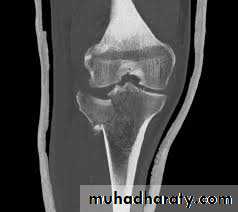

Tibial plateau fractures:

Direct blow or fall from height may cause fracture of one tibial condyle or both.

Lower limb

Fracture lateral condyle is the commonest named as bumper fracture

Patient usually is an adult, the knee joint is swollen, bruises, there is diffuse tenderness and doughy feel of haemarthrosis.

ligaments injuries must be excluded.

Imaging : X-ray

: anteroposterior, lateral & oblique views.

CT -Scan may used to detect amount of depression and comminuation.

Tibial plateau fracture